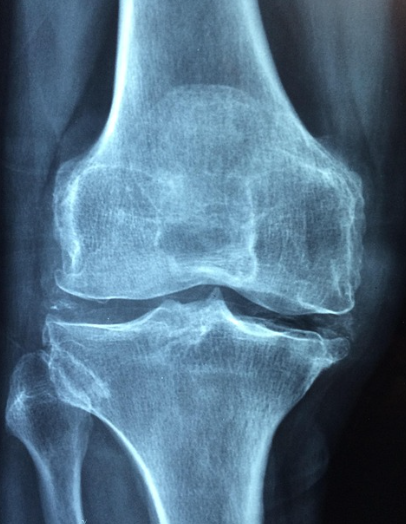

✔ 9. 수술적 치료

약물 치료로 조절이 안 되거나 관절 변형이 심할 때 고려됩니다.

수술 종류

- 관절 재건술

- 관절 교정술

- 인공관절 치환술

수술 시점

- 통증이 심해 걷기·일상생활이 어려울 때

- 관절 변형이 빠르게 진행될 때

- X-ray에서 관절 파괴가 확인될 때

수술은 최후의 선택지이며, 많은 환자는 약물 치료로 충분히 조절이 가능합니다.